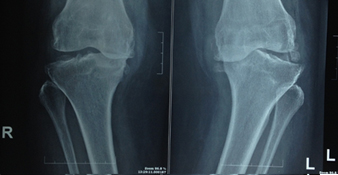

Eight Facts about Primary Knee Replacement

It also means resurfacing. The worn-out cartilage surface is removed and lined with smooth... View More

ARE YOU OR ANY OF YOUR FAMILY MEMBERS CONSIDERING TOTAL KNEE REPLACEMENT?

Before deciding on surgery, have you tried these proven methods? View More